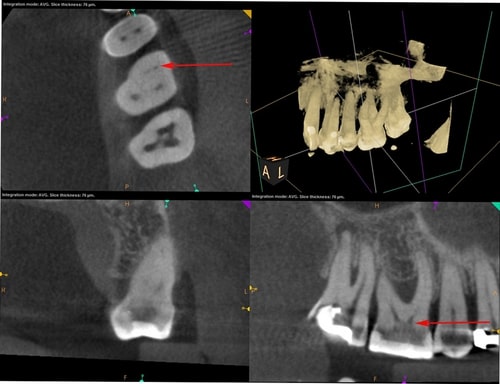

Tehnike pronalaska sekundarnog meziobukalnog kanala

Oblik obrisa pristupnog kaviteta prvog gornjeg kutnjaka trokutast je i smješten u mezijalnoj polovici zuba s osnovom prema bukalno i vrhom prema lingvalno (Slika 3.). Meziobukalni korijen vrlo je širok u bukolingvalnom smjeru, tako da je česta pojava manjeg sekundarnog meziobukalnog kanala. [8] Dno pulpne komore ima određena morfološka obilježja koja su od velike pomoći pri traženju kanala. Obično su na dnu vidljive linije koje vode prema ulazima u kanale i tvore zamišljenu „mapu“, odnosno rostrum canalis. [1] Primarni meziobukalni kanal smješten je blago distalno u odnosu na vrh meziobukalne kvržice, dok je manji sekundarni meziobukalni kanal smješten mezijalno od zamišljene linije koja povezuje primarni meziobukalni i palatinalni kanal, približno na udaljenosti 1 do 3 mm od primarnog. [4] Sam ulaz u sekundarni meziobukalni kanal teško je uočljiv kliničkom inspekcijom zbog dentinskog ramena koje ga pokriva i koje je potrebno ukloniti za lakši pristup kanalu. Osim dentinskog ramena, problem je i meziobukalni nagib ulaza te nagla zavijenost kanala u koronarnoj trećini prema mezijalno što ukazuje na najjednostavniji pristup iz distopalatinalnog kuta. [10] Upravo iz navedenih razloga, kako bi se poboljšala sama pristupačnost kanalu, potrebna je početna priprema i modifikacija pristupnog kaviteta u romboidni oblik uz oprez i minimalnu invazivnost. Istraživanjem je dokazano da je uklanjanje dentina s dna pulpne komore (tzv. troughing) do 2 mm od palatinalnog prema primarnom meziobukalnom kanalu korisna metoda te da su njezine prednosti nadmašile rizik od perforacije. [1] Potrebna je i dobra vizualizacija dna pulpne komore za što se koristi mikroskop, lupe ili barem intraoralno ogledalo s prednjom reflektirajućom površinom. Uz dobru pristupačnost i vizualizaciju lakše je istraživanje dna pulpne komore i traženje ulaza u kanal. Instrumenti poput DG16 Explorer (Slika 4.) ili tanki instrument poput D finder #10 (Slika 5.) od velikog su značaja za lociranje kanala. Iznimno su korisni i ultrazvučni instrumenti koji selektivno uklanjaju kalcifikacije u pulpi i čuvaju dentin od pretjerane štete te otkrivaju skriveni ulaz u kanal. Važno ih je pažljivo koristiti, laganim, kontroliranim pokretima kako bi se izbjeglo pretjerano uklanjanje dentina i iatrogena perforacija. Kod samog traženja kanala, irigacija može pomoći u njihovoj lokalizaciji. Natrijev hipoklorit ima antimikrobna svojstva, osigurava bolju vidljivost, smanjuje rizik od kontaminacije, omogućuje lakši pristup instrumentima te uklanja ostatke organskog materijala. Pulpni ostaci mogu reagirati s natrijevim hipokloritom pri čemu se stvaraju mjehurići, odnosno dolazi do stvaranja kisika, što je pokazatelj položaja ulaza u kanal te potencijalnog postojanja novih, neotkrivenih kanala. Uz natrijev hipoklorit, kao dijagnostičko sredstvo za lociranje kanala upotrebljava se i kemijski spoj 1% natrijev fluorescein. To je oftalmološka otopina koja ima svojstvo vezanja za vezivno tkivo i svijetli kada se izloži plavom svjetlu. Nalapatti i Glassmann predložili su njegovu upotrebu, na način da se otopina aplicira u pulpnu komoru i ostavi da djeluje i reagira 2 minute. [1] Aplikaciju je potrebno obaviti oprezno i paziti na određeni vremenski interval djelovanja, budući da postoji rizik od obojenja zuba. Nakon toga potrebno ju je izložiti plavom polimerizacijskom svjetlu, a kanale promatrati mikroskopom. Važno je obilno isprati pulpnu komoru natrijevim hipokloritom nakon završenog postupka. Na temelju te tehnike, napravljen je i veliki pomak u razvitku mikroskopa, odnosno kobaltno-plavog filtra koji omogućuje još precizniju i jednostavniju primjenu natrijevog fluoresceina. [1] Još jedan vrijedan dijagnostički alat, koji nam omogućuje trodimenzionalan prikaz anatomije jest CBCT (konusna kompjutorizirana tomografija). Ova tehnologija omogućuje bolju vizualizaciju, prepoznavanje varijacija, planiranje samog pristupa, minimalno invazivnu preparaciju te veću predvidivost terapije (Slika 6.). Kliničkom studijom dokazano je da je učinkovitost korištenja CBCT-a u pronalaženju dodatnih sekundarnih meziobukalnih kanala u maksilarnim kutnjacima ograničena te je sam kanal bio prikazan u 33 % slučajeva. [11]